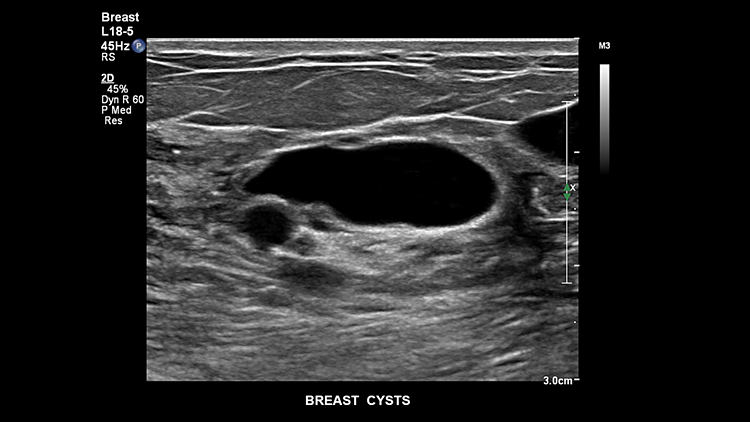

Киста молочной железы, L18-5